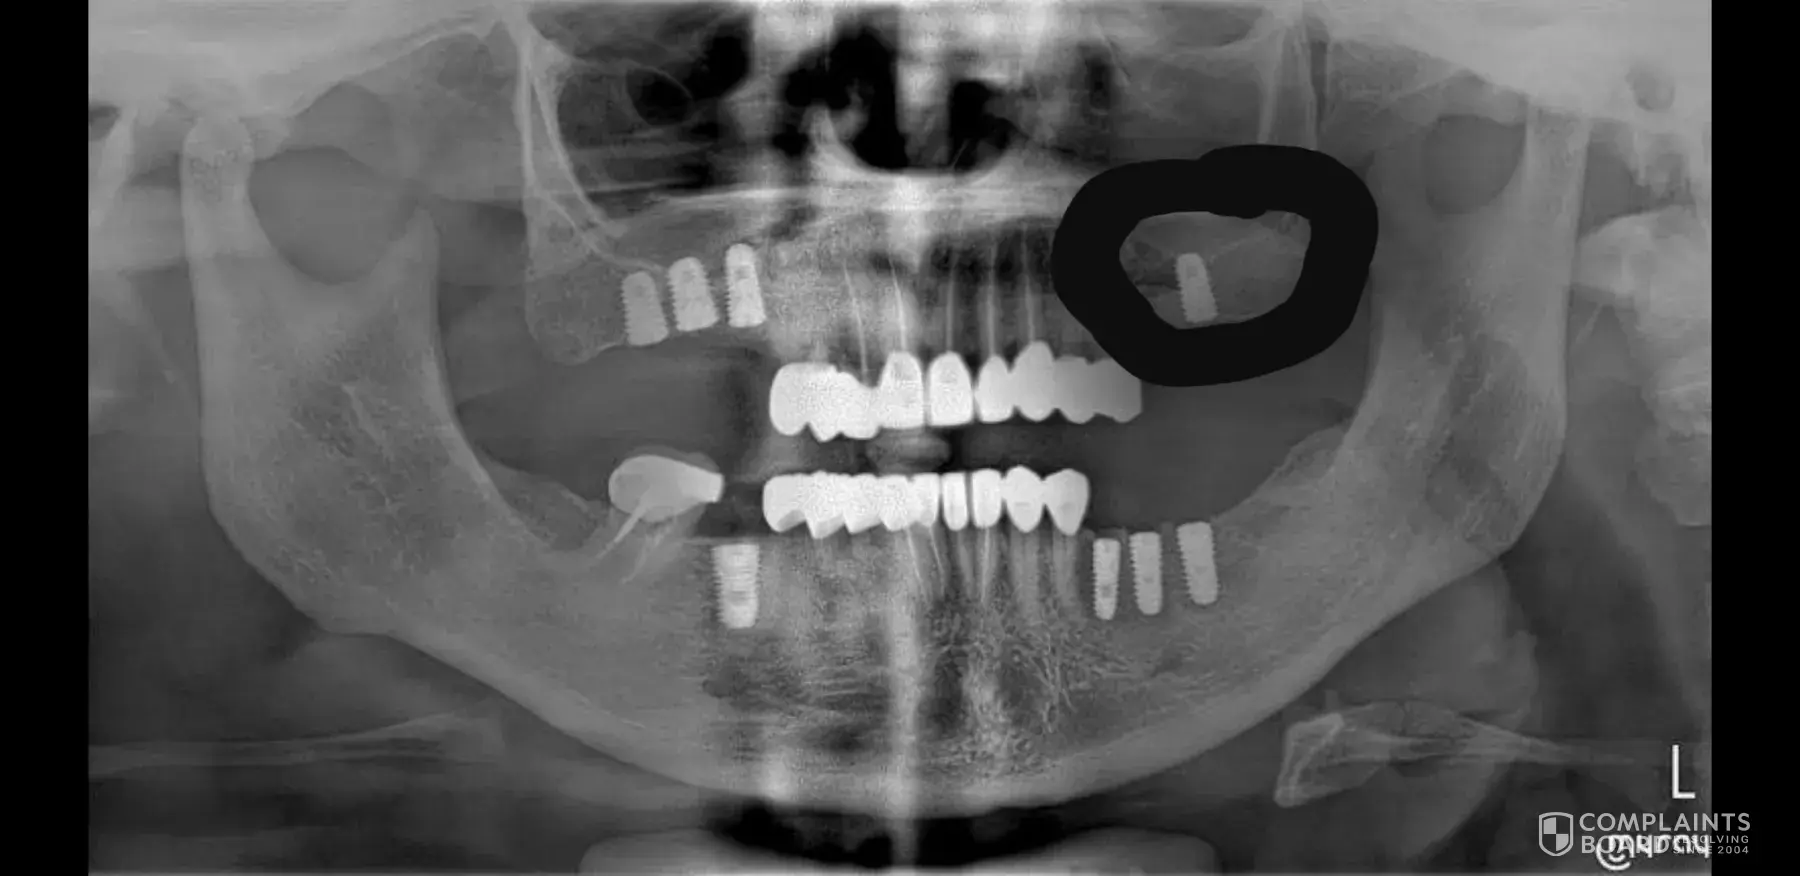

Had bi-lateral sinus lift, 18 crowns and 8 implants, nine root canals. Been suffering from a chronic sinus infection since one week post surgery. Had to be taken to the emergency room in Cancun because of an upper respiratory infection. Found out that they perforated my upper left sinus and one of the lower left implants is infected. I heard the surgeon arguing about the implants. Being too close and perforated. Apparently Dr. Azate plays a bate and switch game with his patients. He'll sneak in additional implants for more money after you agree on one price. He's very dishonest. I'm disgusted because I brought it to their attention and they did nothing to address the issues. Today I just had oral surgery to fix the implant that got infected. Cost an additional $1200. And may have to have the implant removed. My total so far is $19, 000 for the work. An additional $3000 for the emergency room because of the sinus infection. $300 extra meds, in Mexico, extra hotel stay because the rude receptionist, didn't schedule my crowns until the day before departure. Additional 2000 for hotel. Additional 600 for flight changes, today's surgery 1200, and 600 for urgent Care for sinus infection last week. Been on antibiotics for at least 30 days. I'm very angry and my attorney will deal with them. The red flag was they keep changing their name. That's means they are being sued by other patients. Really crooked. STAY AWAY FROM THESE CRIMINALS!

I will start my story from when I decided to get my teeth fixed and overcome my dentist phobia. My finances after bad decisions made were in horrible shape and I could not afford a decent dentist in the US, the cost was prohibited... who has 60, 000 + cash on hand? I decided to search the internet and came across a dentist not foo far from South Carolina... sunny Cancun! His name is dr German Arzate. If I knew then what I know now! After numerous emails with Patricia Arciniega the coordinator at the clinic and after numerous assurances that he was the absolute best of the best in the field of dental implants and with an impressive certificate from the US and recommended by "top dentists" like Dr Shankar, Dr. Piermatti, Dr Minichetti, Dr D'Amore, I decided to go. After all all of those doctors represent the AAID and the ABOI. He boast certificates received by them in the US! My appointment was on July 1st 2019 with surgery on July 2nd. My son accompanied me and we were put in a small, dark, hot room to pay the almost 19, 000 dollars... I should have paid attention to the signs. The credit card kept on getting rejected and the secretary kept on trying and asked my son to keep on calling the bank until the transaction went through. What a big mistake... I wanted to get up and leave but she assured me that was just a glitch. I didn't find the clinic clean or the staff knowledgeable enough to make me feel comfortable nor the doctor for that matter. I actually found him to be arrogant and a big talker. He acts like he has seen it all and done it all. More to come on that. He has all of his staff trained to lie right to your face.. you know the type... darling, love, sweetheart we so happy to see you, you are in great hands, Dr Arzate is the best! They are the front field of the castle of lies... The "fluffers" as I call them. I don't know why to this day I defended him when I first came home. I guess I was scared he would leave me with half job done. I didn't even tell my own husband how bad or the pain I was feeling.in retrospect it was very foolish of me to suffer by myself. I say half job because as soon as I came back to the US... something was wrong, I had pain, unusual pain, redness and my gums were swollen, when I used the water pick, blood was coming out. I contacted Patricia Arciniega and after a series of emails I was told the doctor wanted me on antibiotic and to have my dentist here take a look at my infection... I contacted dr Hehr, top surgeon in the field here in SC... and he was shocked at the work that was performed. I was devastated, I went home with antibiotic for my infection that dr Hehr after much begging finally prescribed after I showed him the recommendation of Dr Arzate Clindamycin 300mg 3 times a day for 28 days. I became very depressed, I lost the only money we had saved... so depressed to the point I tried to commit suicide on July 26. Dr Arzate after convincing him I had problem with my implants, asked me to go back and so I did... more money spent on flight and hotel and I arrived on September 11 This time I was alone... He checked me out and told me surgery to remove one implant was scheduled for the next day and I had to pay for the anesthesia. I returned the next day and I was put to sleep. I felt pain during my surgery, I remember putting my hand inside my mouth several times and when I woke up, the left side of my gum was so swollen it literally was touching my cheek. Dr Puly apologized to me saying that it was her fault and then I also complained about the implant on the top left that was taken out and now there was a new one really crooked that was painful. They told me not to worry about it because the surgery was really fresh. Dr Arzate came in the next day showing me X-ray with a big grin telling me he did me a big favor and gave me a big present inserting 2 extra fat implants! Wait... I did not ask nor did I want more implants! Now... I was waiting for the immediate load again to come home with, instead they worked on sending me home with denture finding the excuse that my gums needed to heal for a couple of months. Every day I was there 16 days to be exact, I kept on complaining about my swollen gum and my implants hurting and of course they kept on telling me (dr Puly and Dr Arzate) that it was normal. At one point my denture was horrible, the 2 front teeth were off to the side by a lot (see picture) he was also trying to fix the bottom by pulling it with wire to make it fit... a complete disaster. After I came back to the US, my pain increased, pus started to come out, I couldn't wear the denture because the implants were hurting, I emailed, sent videos and in few words it was either my fault (because dr Arzate is the master), go to a dentist to have the implant removed or just take a plane and they would check it out. Easy right? Sure if I lived around the corner or have endless money hidden under the mattress. I showed them on the video that my gums were not even closed right, they did not put the stitches in the right places and they left them open so bacteria and food would go in... He had the audacity to write me a response saying... I am happy to see the implants are in your gums strong and you saw and verify when you were here that the implants were put in the correct place... ME? Really? How do I know? More Clindamycin 300mg, more pain... I was on that medication for a total of 56 days! The only thing I know for sure now is that your degree in Mexico as a "doctor" is not recognized in the USA. I am sure you could not even be a dental hygienist here without going back to school. I have come to realize that all this is a big huge scam including the ABOI and AAID. If you pay good money to Dr. Minichetti or Dr Shankar you get your certificate. This is something that NEEDS to be investigated by the medical board as the biggest scam I have ever come across. I am sure that it is good for dentists here in the US that want to continue their education, but to give this certificates to "dentists" abroad is like giving a loaded gun to a child and ask him to go play in a yard full of kids. I went to see another surgeon here, Dr. Mark F. Yampolsky, DDS and after taking X-Ray he recommended for 6 implants to be removed because either infected or situated wrong. Because I was still under warranty, I decided to go back to Cancun and have them removed. I endured again the expense of the plane ticket and hotel and I went back to the clinic where this time I brought my IPad to record the whole conversation. Dr. Maria Paula Villalobos and Patricia Arciniega were in the room telling me that my doctor was wrong and that dr. Arzate was in the hospital with kidney stone emergency (found out from a photo he was out of the Country). They told me that maybe one needed to be removed but they would check every single implants and planned surgery for the next day. I told them specifically that IF they needed to remove more than 2, to please remove all of the one my surgeon here in the US recommended. When I woke up from the surgery not only they removed just 3 but they put 4 more that I did NOT ask or wanted or gave my permission. This was done against my will. I feel raped, violated, they had no right to do that. As an aside note... I had my recording on the whole time during the surgery without them knowing about it. Every time I went to the office I recorded every single conversation. I am glad I did that because they had no problem telling me they record conversations with patients... now I have mine. I know it's illegal here in the US unless you tell the other person they are being recorded, but I guess in Mexico the law is different. They talked about other patients divulging their name and what a pain to deal with they were. Unprofesssional! I contacted Dr. Shankar and he said he was going to "Mediate" and to contact him after my return... he blocked me when he found out who the doctor in Cancun was because he is one of his best friend who hosts one of the AAID maxi course in Cancun... like I said... it's stronger than a mafia clan. I am still to this day in so much pain, the implants they left are still infected, they hurts and the people who give these "doctors" these certificate to operate under the false pretense they are trained in the US are filling their pockets to the tune of 100's of thousand of dollars... They have created a black hole that nobody can penetrate. It's a strong clan but somebody has to step up and do something. The procedure I had done it's called All-on-four and supposedly was invented by Dr Paulo Malo... well Dr. Arzate is taking credit and say he is the inventor (yes I have it on video) and it's the reason why I went to him in Cancun... who better to do the procedure than the inventor himself? I am beside myself how can this happen? When I confronted them about dr. Arzate not having kidney stones they blocked me from messaging them on FB. I have an appointment set up for February 24 2020, I want to have to pull all of the implants taken out.